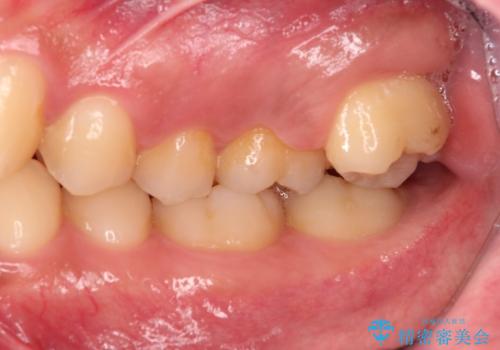

奥歯はすれ違ってしまっていました。

上顎両側7番(一番奥の歯)はすれ違っており、虫歯になっていました。